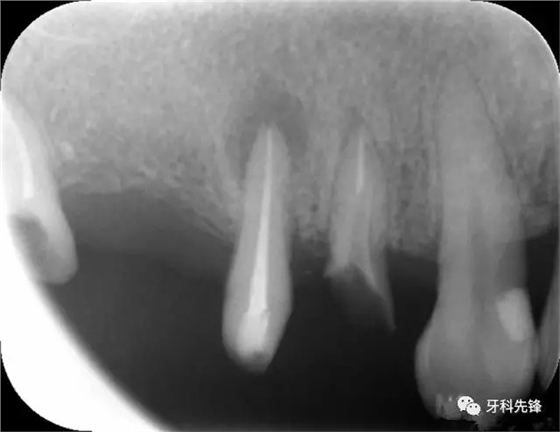

圖8治療術(shù)后X光片